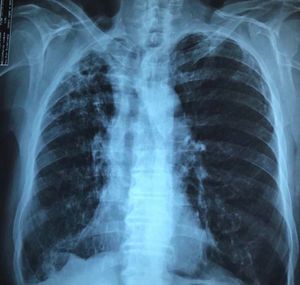

What's your diagnosis?

Bronchiectasis on the apex of right lung, fibro infiltrat and also tracheal deviation. It suggest maybe some of chronic pulmonary infection..😀

Dextrocardia.

Clavicle fracture

Tb and upper and lower right lung partial collapse